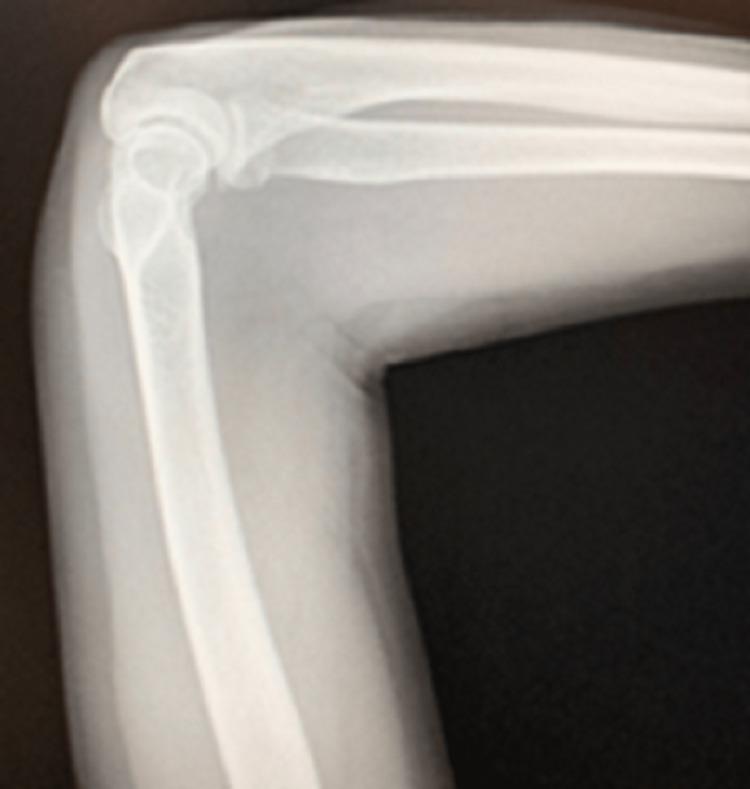

The standard convention for diagnosing bone fractures is through radiography. However, radiography can miss fractures depending on the type of injury or if human error is present. This may be due to improper patient positioning leading to superimposing bones being captured in the image, obscuring pathology. As of late, ultrasound has been gaining traction in terms of its utilization for diagnosing fractures, which radiography can miss at times. Here we present a case of a 59-year-old female who was diagnosed using ultrasound with an acute fracture that was initially missed on X-ray. We present a case of a 59-year-old female with a past medical history significant for osteoporosis who presented to an outpatient clinic for evaluation of acute left forearm pain. She reported sustaining a mechanical fall forward to the ground three weeks before bracing herself with her forearms, immediately developing left upper extremity pain lateralized to the forearm. Upon initial evaluation, forearm radiographs were obtained and showed no evidence of acute fractures. She then underwent a diagnostic ultrasound that showed an obvious fracture of the proximal radius, distal to the radial head. Upon reviewing initial radiograph films, it was evident that the proximal ulna was superimposed over the radius fracture as a proper neutral anteroposterior view of the forearm was not taken. The patient then underwent a computed tomography (CT) scan of her left upper extremity, which confirmed the presence of a healing fracture. We present a case in which ultrasound is an excellent adjunct when a fracture cannot be identified on plain film radiography. Its utilization should be well-known and considered more often in the outpatient setting.

诊断骨折的标准惯例是通过X线摄影。然而,根据损伤类型或是否存在人为误差,X线摄影可能会漏诊骨折。这可能是由于患者体位不当导致图像中出现骨骼重叠,从而掩盖了病变。近年来,超声在骨折诊断中的应用越来越受到关注,而X线摄影有时会漏诊这些骨折。在此,我们报告一例59岁女性病例,其急性骨折最初在X线检查中漏诊,但通过超声得以诊断。我们报告一例59岁女性,有骨质疏松病史,因急性左前臂疼痛到门诊就诊。她报告说,在向前摔倒并以双前臂支撑身体三周前,立即出现左上肢前臂外侧疼痛。初步评估时,拍摄了前臂X线片,未显示急性骨折迹象。随后她接受了诊断性超声检查,显示桡骨头远端近端桡骨明显骨折。在复查最初的X线片时,很明显由于未拍摄前臂正确的中立前后位片,尺骨近端重叠在桡骨骨折处。患者随后接受了左上肢计算机断层扫描(CT),证实存在愈合中的骨折。我们报告这样一个病例,当在平片X线摄影中无法识别骨折时,超声是一种很好的辅助手段。其应用应该更广为人知,并在门诊环境中更频繁地被考虑。